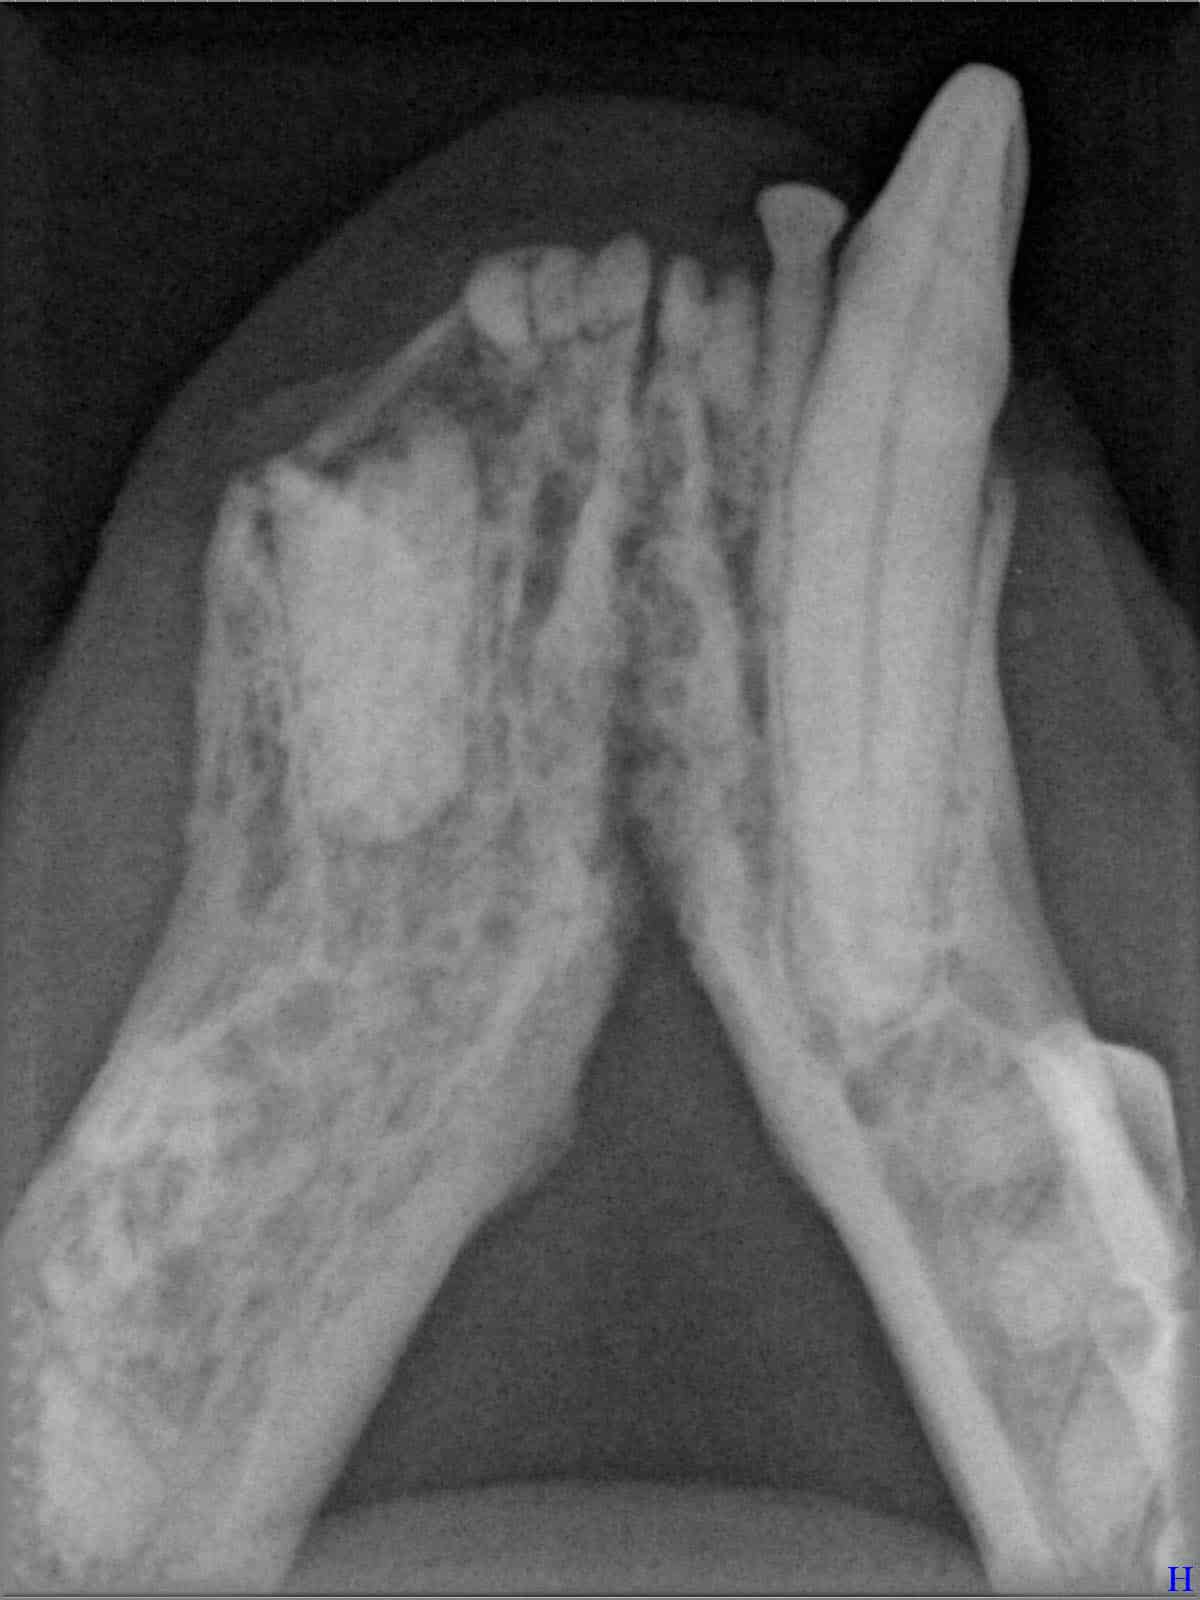

Das sehen Sie von außen – so sieht es auf den Röntgenbildern aus.

FORL Katze Röntgenbild

Röntgenbilder